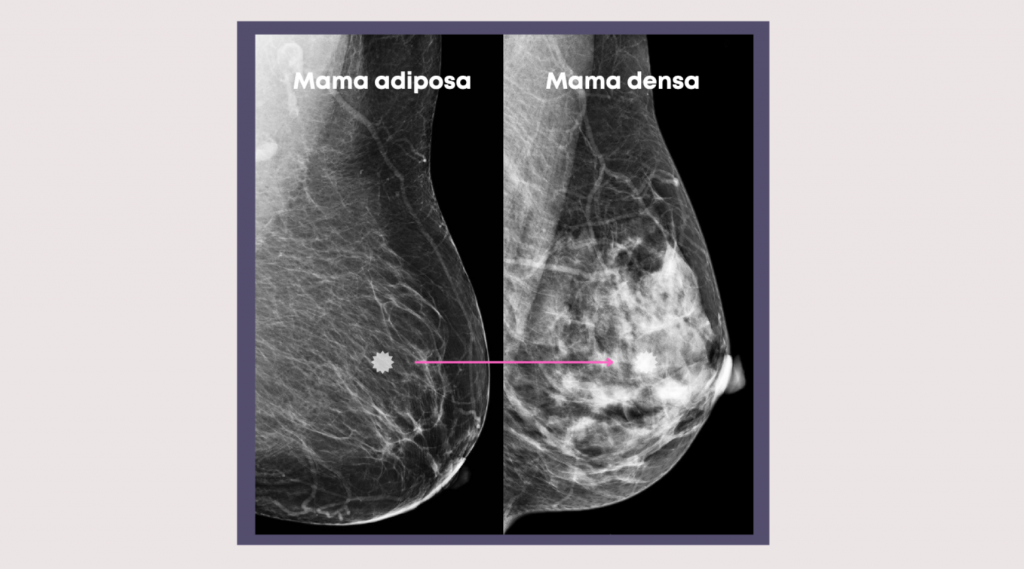

¿Qué es la mama densa y por qué es importante conocer tu tipo de tejido mamario?

Cuando hablamos de prevención del cáncer de mama, uno de los conceptos que más dudas genera es el de la mama densa. ¿Sabías que conocer tu tipo de tejido mamario puede marcar la diferencia en la detección temprana del cáncer de mama? Hoy te explicamos de manera sencilla qué significa tener mamas densas, cómo se detecta y […]